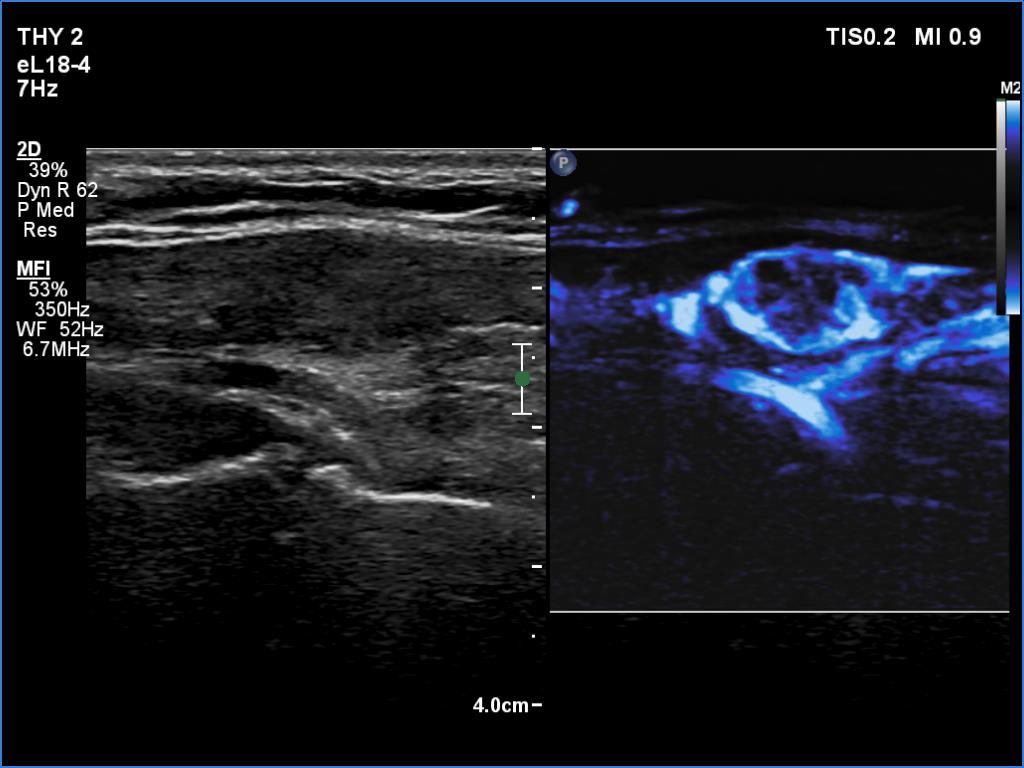

Second examination 3 months later (ultrasonographic picture 5)

Right lobe, longitudinal scan, microflow imaging. The lesion is rich in vessels while the extralesional part has a decreased vascularity.